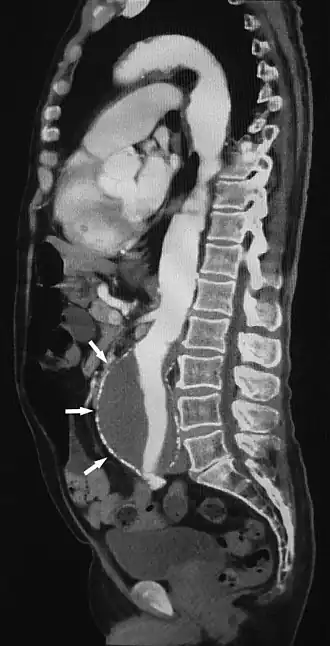

![]() Sagittal thin slice of a computed tomography angiography abdominal aortic aneurysm (AAA) (arrows) | |

Aorta and great arteries

CTA can be used in the chest and abdomen to identify aneurysms in the aorta or other major blood vessels. These areas of weakened blood vessel walls that bulge out can life-threatening if they rupture. CTA is the test of choice when assessing aneurysm before and after endovascular stenting due to the ability to detect calcium within the wall.[3] Another positive of CTA in abdominal aortic aneurysm assessment is that it allows for better estimation of blood vessel dilation and can better detect blood clots compared to standard angiography.[4]

CTA is used also to identify arterial dissection, including aortic dissection in the aorta or its major branches. Arterial dissection is when the layers of the artery wall peel away from each other; this causes pain and can be life-threatening. CTA is a quick and non-invasive method of identifying dissections and can show the extent of the disease and if there is leakage.[4]